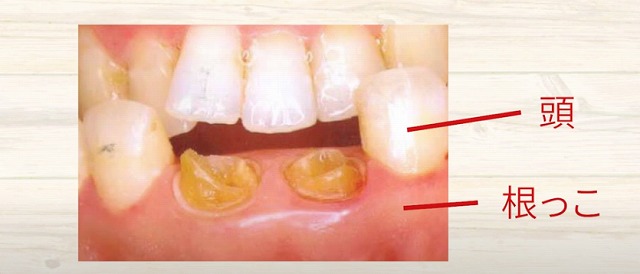

歯はこのように

手鏡等で見ると見えますが、

見えているのは実は

歯の頭だけが見えています。

そして

その下には長い歯の根っこがあって

硬い骨で覆われています。

さらに

薄い歯茎が骨の上に乗っているんですね。

このように

歯の頭があって歯の根っこがあります。

中に

神経や血管があるわけです。

歯の神経の治療をするにあたって、

この歯の頭が邪魔になります。

ですので、

頭をスパーンて

削って落としたりするんですね。